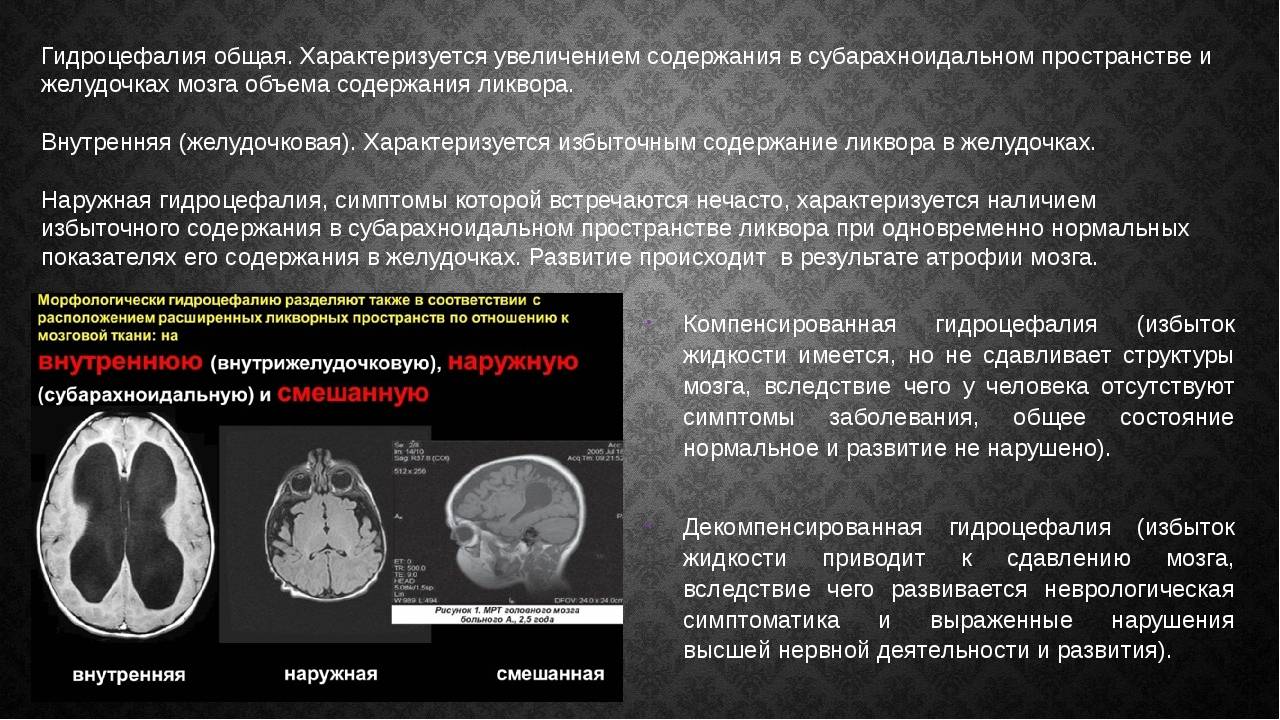

Признаки умеренно выраженной наружная

Признаки умеренно выраженной наружная 113 фото